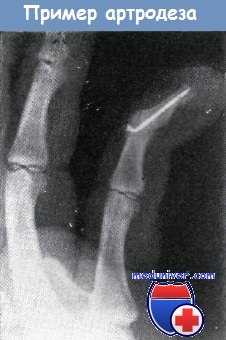

После застарелого повреждения сухожилия сгибателя мизинца у мужчины средних лет произведен артродез II межфалангового сустава под углом в 30° с помощью временной проволочной фиксации.

Состояние пальца оказалось настолько удовлетворительным, что больной начал работать до удаления проволоки, и, вместо удаления ее через шесть недель, она была удалена только через 4 года.

На рентгеновском снимке видно, что между средней и концевой фалангой образовался хорошо выраженный костный анкилоз.

Проксимальный конец проволоки искривлен, что является следствием рано начатой работы.

Удаление проволоки в этом случае, разумеется, осуществлять с проксимального конца. Этот случай лишний раз подчеркивает необходимость рентгенограммы перед удалением любой проволоки или спицы.